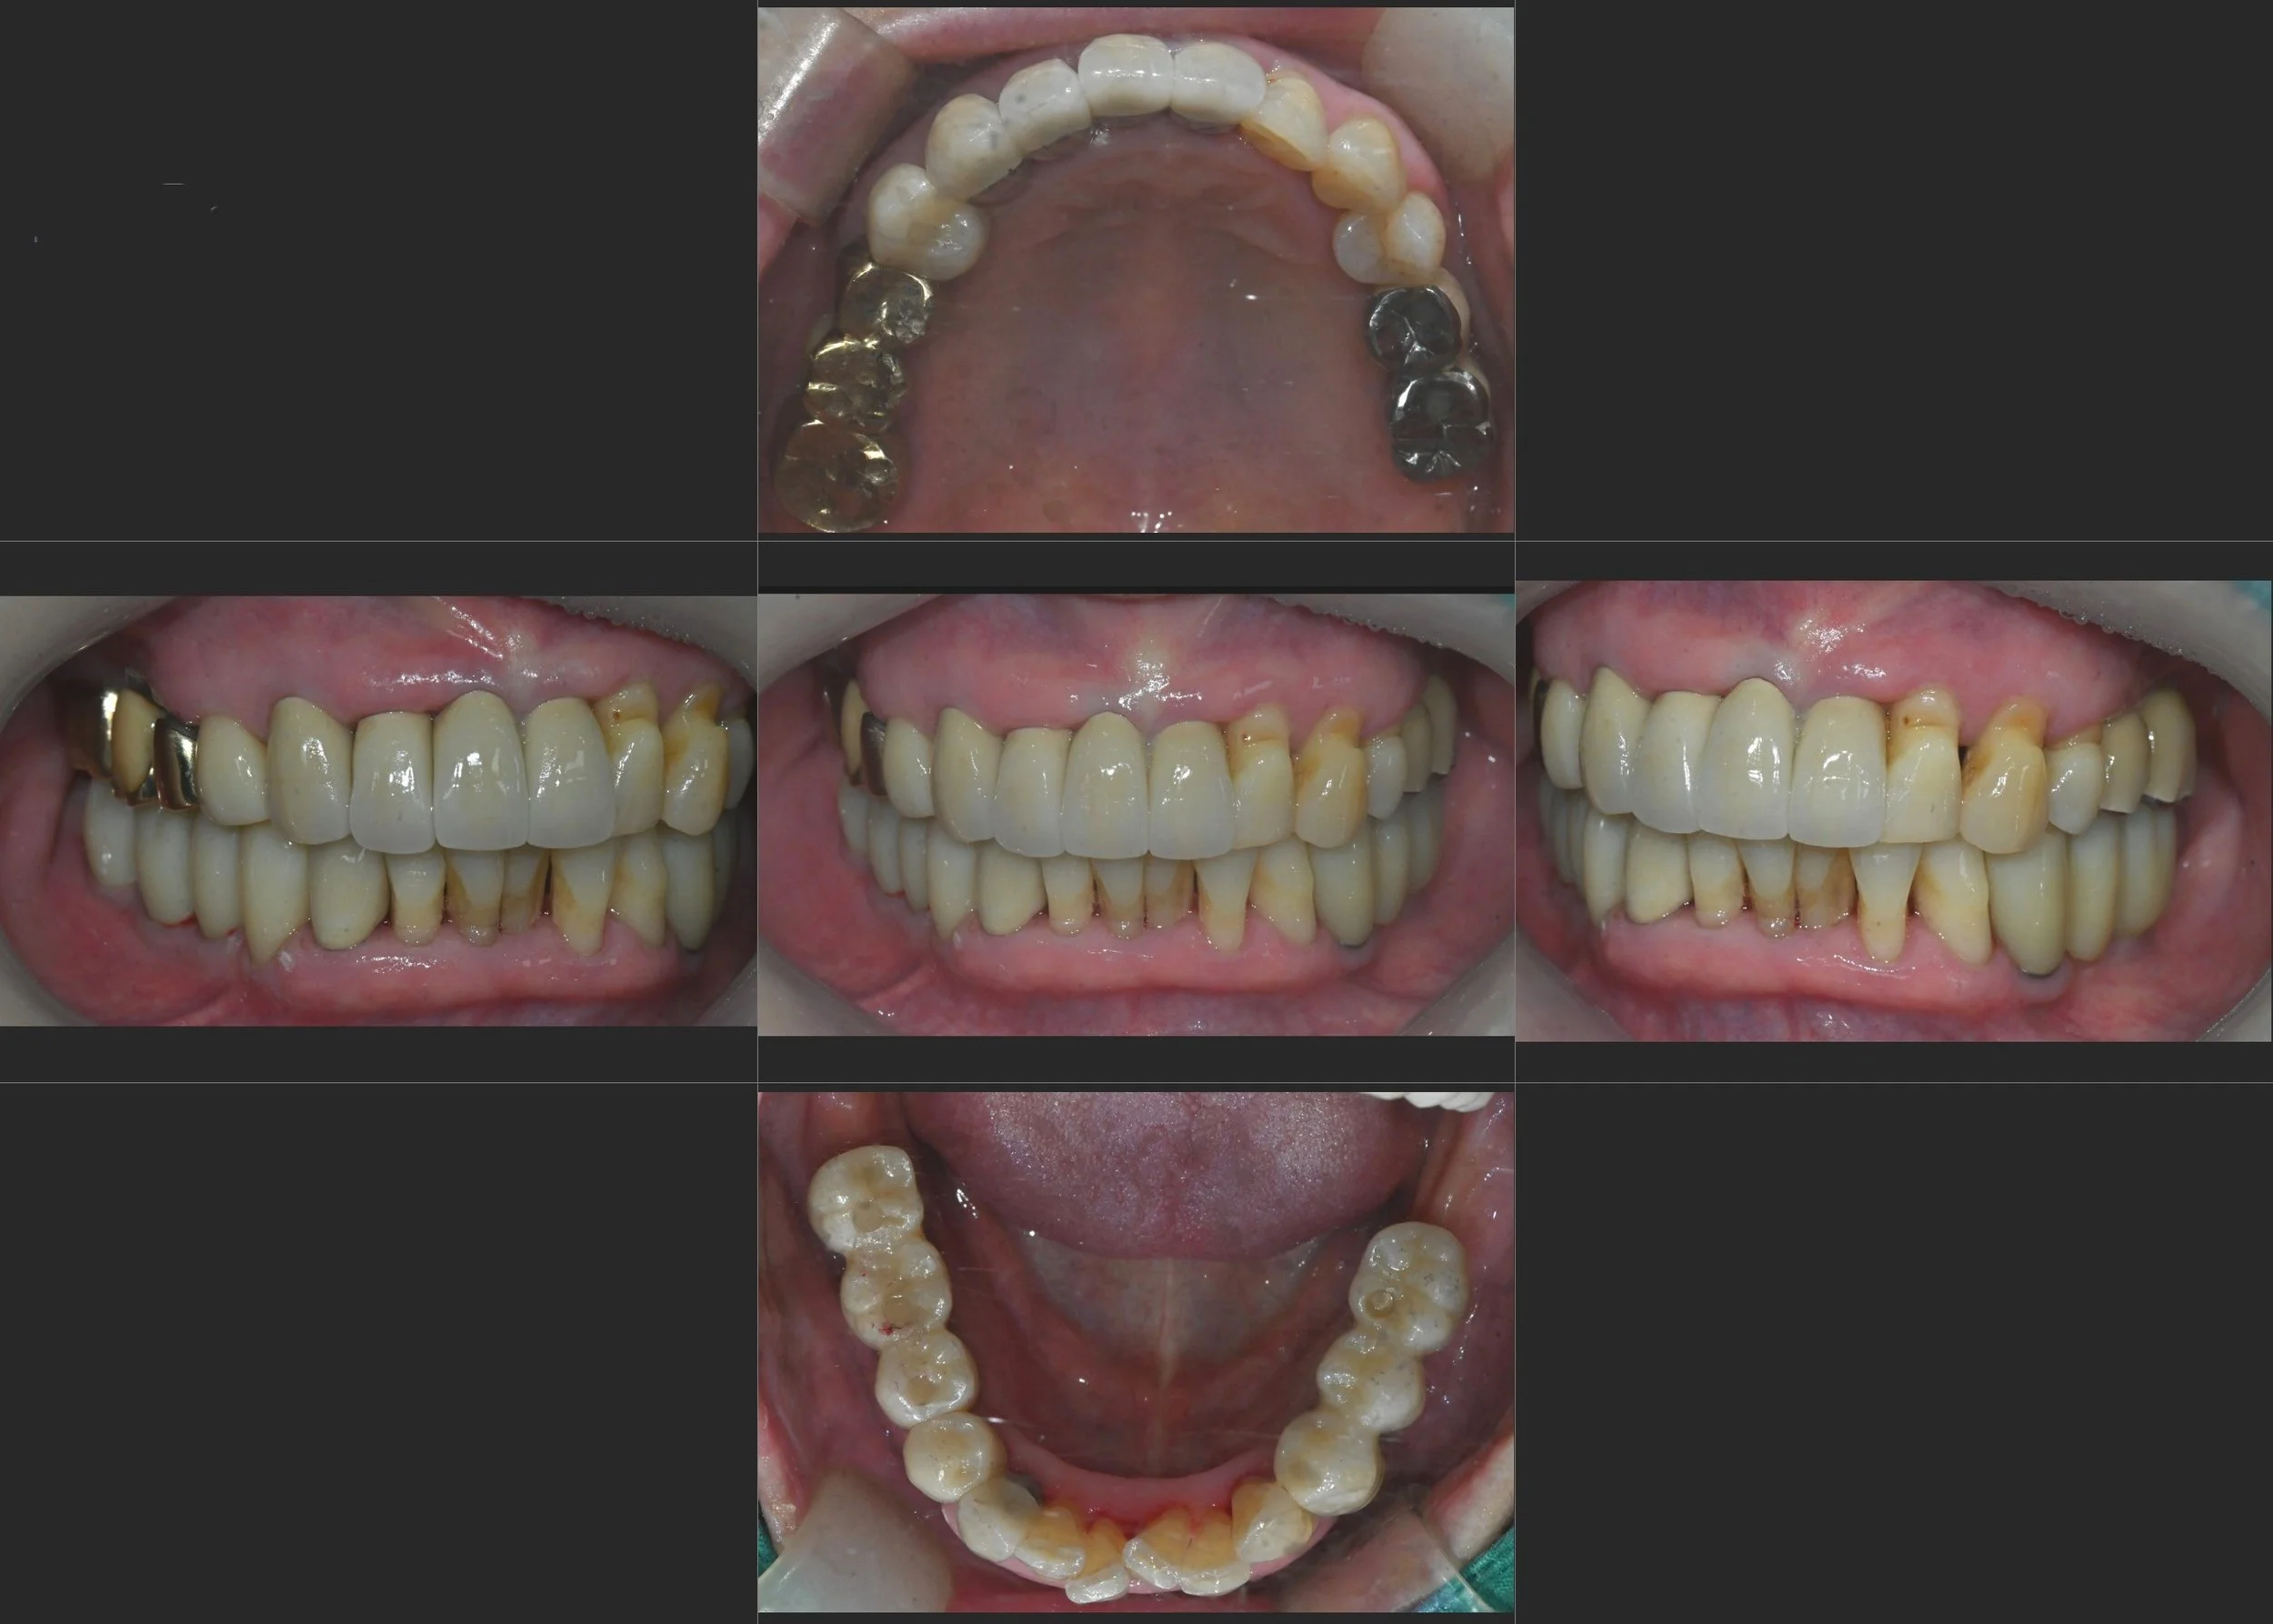

• Pre-operative Intraoral Views Initial views revealing the extent of dental neglect, poor prosthetic condition, and collapsed posterior support.

INTRA ORAL - BEFORE